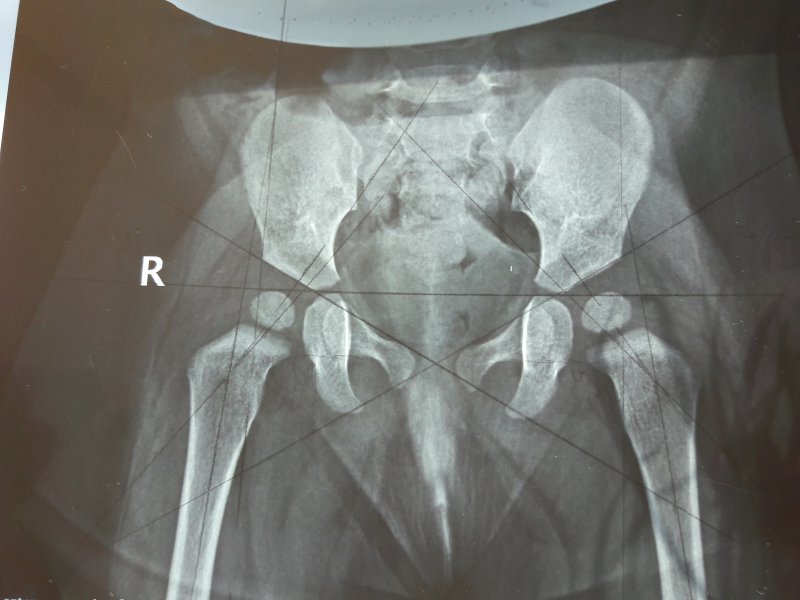

Рентген ТБС: Нормальные показатели

Раздел: Необычные решения